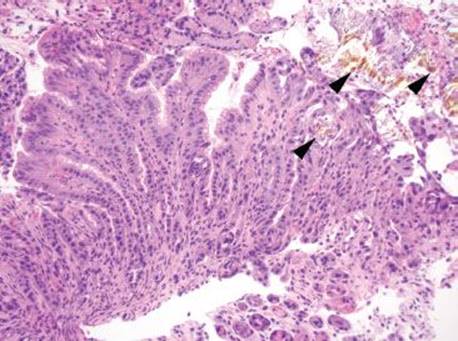

Gastric iron deposition is seen in up to 3.8% of upper tract biopsies (Fig. 2.228).23,24,183–185 In a study of 500 gastric biopsies, the deposition was demonstrated in three generalized patterns. Pattern A (also referred to as “nonspecific gastric siderosis”) was the most common subpattern and involved 2.2% of specimens (Figs. 2.229 and 2.230). This subpattern was associated with prior mucosal microhemorrhages, and the subtle depositions were predominantly identified within macrophages and stromal cells of the lamina propria. Pattern B (also referred to as “iron pill gastritis”) was seen in 0.8% of the biopsies and was consistently associated with ferrous sulfate therapy. This deposition was coarse and crystalline and predominantly identified in the extracellular and most superficial aspect of the biopsy (Figs. 2.231–2.234). In this subpattern, the background mucosa had a reactive gastritis/gastropathy pattern with erosions, ulcerations, and fibrino-inflammatory exudate common. In a separate study of 1,300 gastric biopsies, a similar “iron pill gastritis” injury pattern was detailed.184 This latter group reproduced the identical iron deposits in the laboratory by oxidizing ferrous sulfate tablets, providing clear evidence for the iron origin of these deposits. The mechanism of injury is a bit unclear in this subpattern. Some speculate that the iron pill has a direct caustic effect on the adjacent mucosa, whereas others suggest that the iron deposits may simply colonize previously injured mucosa. Pattern C (also referred to as “gastric glandular siderosis”) was the least common pattern, involving 0.6% of the specimens. This subpattern was associated with iron overload settings, such as hereditary hemochromatosis and multiple blood transfusions. The characteristic deposits were subtle, uniform, and identified in the deep antral and oxyntic glands (Figs. 2.235–2.239). The iron deposits can be highlighted blue with a Prussian blue iron special stain. Recognition is important to help prevent further injury and potential stricture formation (pattern B), to suggest pertinent iron overload evaluation (pattern C), and to avoid overdiagnosing the marked reactive epithelial change as dysplasia.

Figure 2.233 Iron pattern B/“iron pill gastritis”. Iron is seen encrusted in the superficial foveolar epithelium.